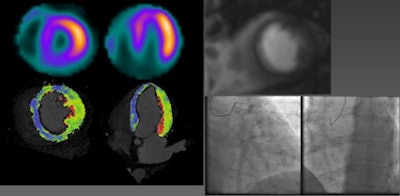

| Above, 50-year-old man presenting with chest pain underwent stress myocardial perfusion SPECT and CT, which showed corresponding areas of perfusion defects, as did MRI. Right, patient underwent cardiac catheterization for stenoses in the left anterior descending and right coronary arteries. All data and images courtesy of Markus Weininger, MD. |